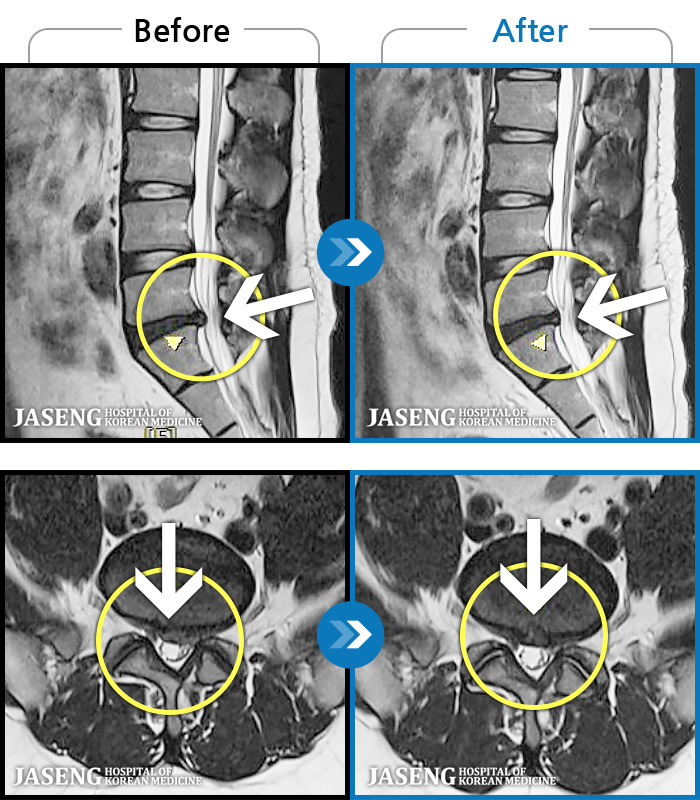

ȯںп Ǹ ǿ ԿǾ, ο ġ ۿ Ƿ ġḦ Ͻñ ٶϴ.